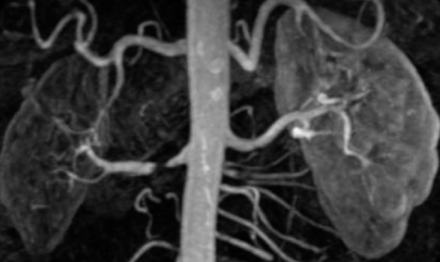

- Name 2 etiologies of condition: Z Atherosclerosis, Fibromuscular dysplasia

- Pathology in the image: Renal Artery Stenosis

- Treatment option: Angioplasty + or - stent